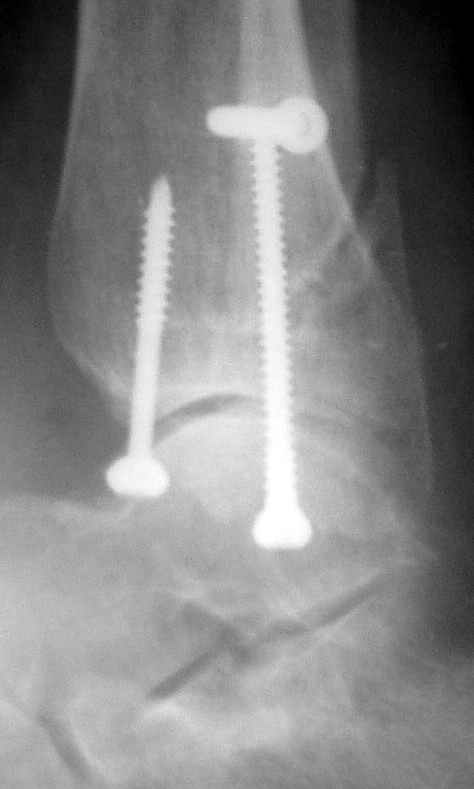

Боковой через месяц